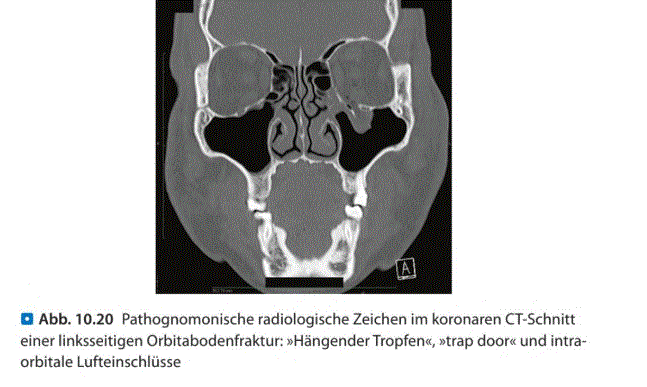

Q

Welche Art der Aufnahme

Was auffällig